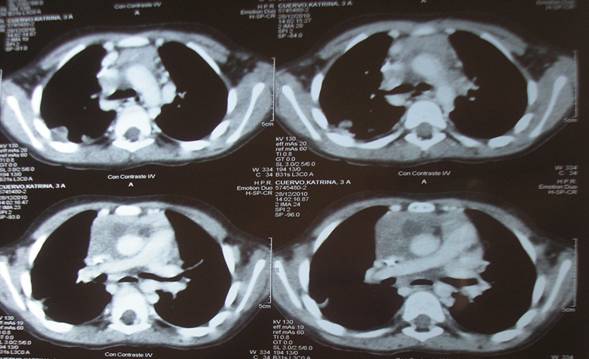

Paciente de sexo femenino, pre-escolar de 2 años y 10 meses, coordinada para exéresis de masa mediastinal anterior. AEA: Sin antecedentes patológicos previos, consulta en emergencia por cuadro de 7 días de evolución con tos seca, escasa, sin rinitis ni fiebre, agrega en la evolución edema de cara y miembros superiores. Vista en policlínica, se le indica antihistamínicos con leve mejoría de los síntomas, a las 48 horas agrega dolor abdominal difuso, de moderada intensidad acompañado de náuseas, adinamia y anorexia por lo que re consulta. Tránsitos digestivos bajo y urinario conservados. Examen físico: se presenta apirética con edema de cara y miembros superiores, frialdad periférica con coloración rojo vinoso de dicho territorio que dejan godet. A nivel respiratorio: polipneica, sin tirajes, buena entrada de aire, sin estertores. A nivel cardiovascular: PA100/75, RR 156 cpm, no soplos. IY sin RHY. Abdomen: Hepatomegalia dolorosa. La paraclínica básica de valoración inicial fue normal. Se realizaron pruebas serológicas para virus respiratorio las que fueron negativas. Ecografía de abdomen que informó: hepatomegalia leve a moderada. ECG: Taquicardia sinusal de 159cpm. Radiografía de tórax: evidenció un aumento del índice pericardio-torácico y signos de edema pulmonar con redistribución del flujo hacia los vértices. (Figura 1)

Figura 2: TC (superior e inferior), que muestra gran masa mediastinal anterior y sus relaciones con grandes vasos y vía aérea.